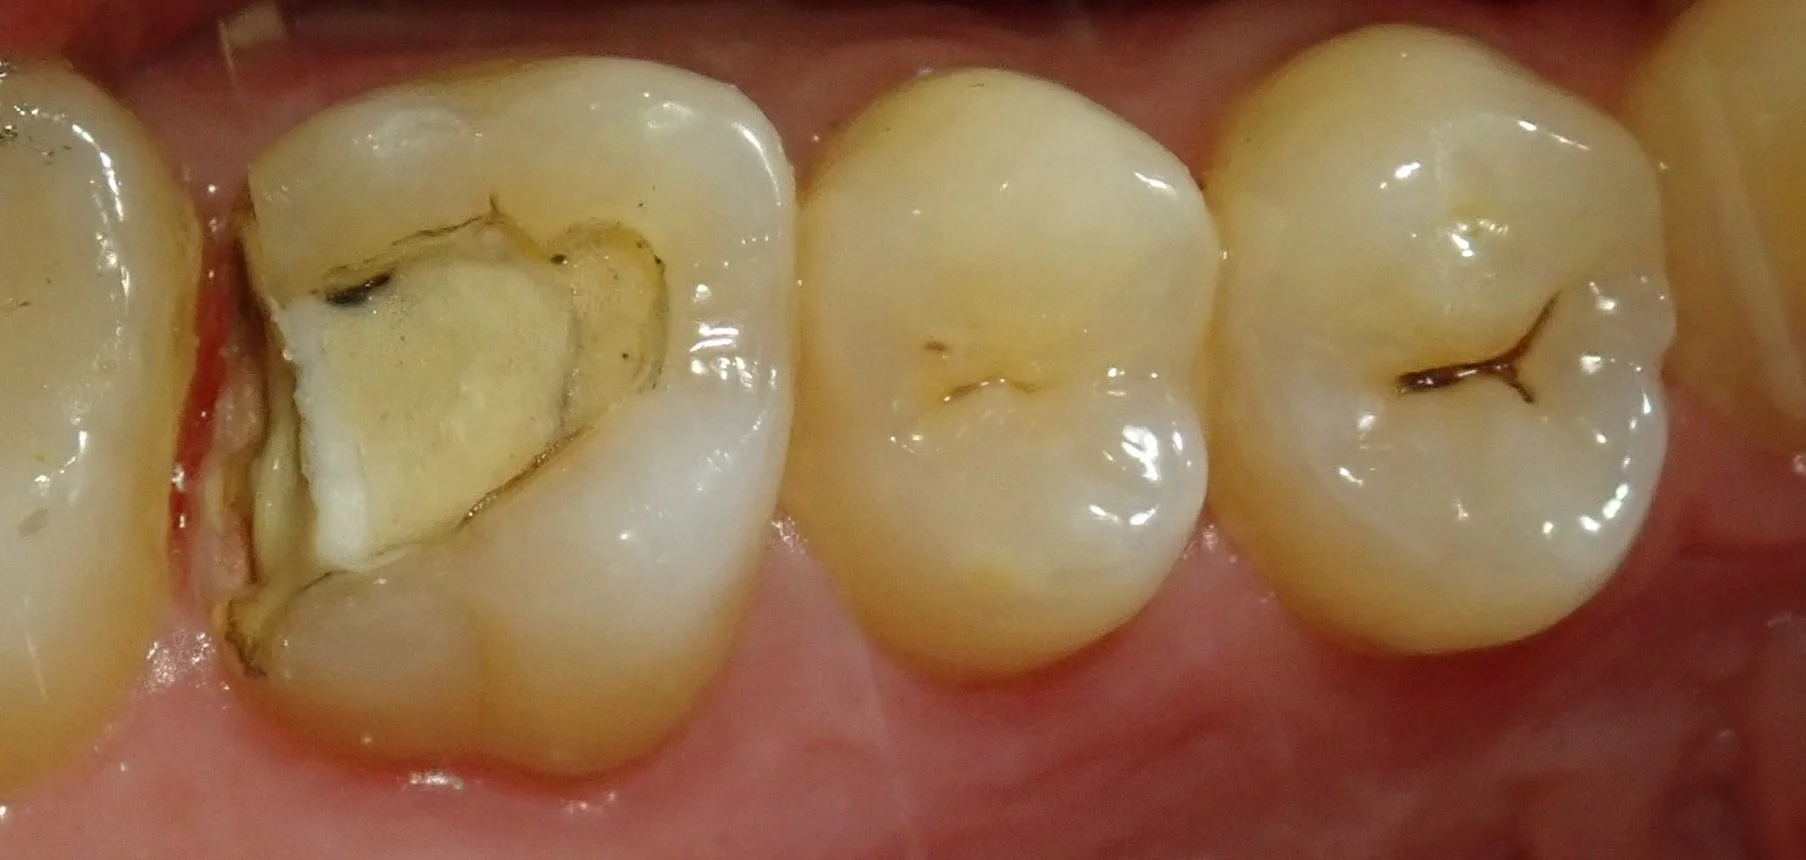

まずはいつも通り、術前写真から。

この金属部分が虫歯になってしまっているので、ここを治療していきました。

元々入っている金属自体の適合は決して悪くはありません。

ですが、金属の詰め物被せ物は歯に直接くっつけることが出来ませんので、セメントを介して歯にくっつけることになります。

ですが、そのセメントも長い年月をかけてボロボロと取れていき・・・

そこの隙間から虫歯になってしまうという事が多々あります。